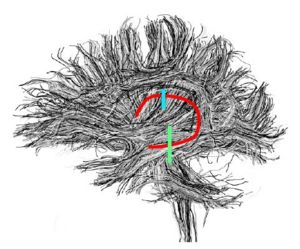

Fornix

ROI 1 was drawn on the sagittal slice, 5 slices superior to the anterior commisure (Fig. 8 & 10). ROI 2 was drawn on a coronal slice where the crux of the fornix was present. It was not always the same slice for both sides (Fig. 9 & 11).

Figure 8. Axial View of ROI 1

Figure 9. Coronal View of ROI 2 (left=11, right=13)

Figure 10. Sagittal View of Fornix, ROI 1 (both left and right)

Figure 11. Sagittal View of Fornix, ROI 2 (right)

The color coding of the resulting ROIs is as follows:

ROI 1: Left & Right (7)

ROI 2: Left(8) - Right(6)